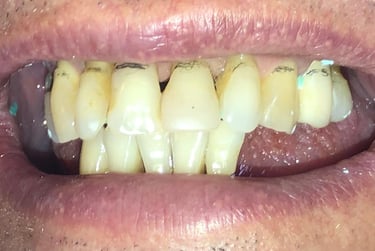

Aspecto Clínico Inicial - Fotografias originais — nenhuma contém retoques

Coroas em Dissilicato de Lítio

Todos os caso a seguir estão associadas a clareamento dentário

Antes